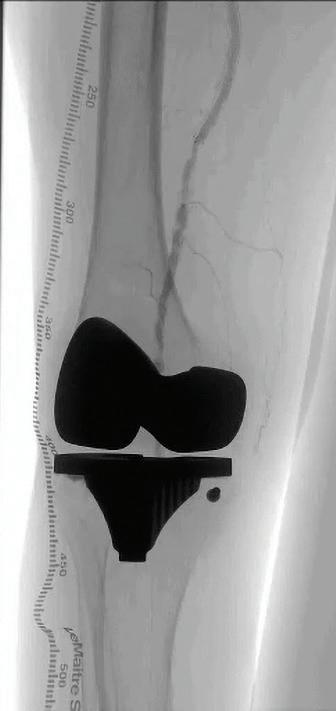

Embolization is often not very familiar to vascular surgeons. With the exception of type II endoleaks, these cases often get referred to interventional radiology (IR). As a result, there is little—if any—exposure to these procedures in vascular training. Once in practice, we don’t really think about them, despite the fact that they fit nicely into an outpatient practice.

At the hospital my practice covers, there is not much of an IR presence, so vascular surgery provides the emergency embolization services. Between the cold legs and ruptured aneurysms, we are also handling the gastrointestinal bleeds, ruptured spleens and postpartum hemorrhages. This has resulted in increasing comfort with these procedures. The anatomy and technical details are not dissimilar to what we do on a daily basis.

CORNER STITCH

In addition to the hospital practice, we also have a busy office-based lab (OBL). In the context of this setting, we were asked by a gynecologist in the area about providing uterine artery embolization (UAE) for fibroids. Given our exposure to embolization procedures in the inpatient setting for emergencies, this felt like a very reasonable extension of our outpatient practice.

UAE has several characteristics that make it an ideal procedure for the outpatient setting. It is purely elective, which makes it practical to schedule. The patients are generally younger and lower risk than the typical vascular patient. The procedure itself is also low risk, with only relatively small sheaths required and the option for radial access. UAE also tends to be fairly routine and predictable. In a

setting where significantly prolonging the day is not an option, there is a benefit to knowing, with a reasonable degree of certainty, how long the procedure will take. Most importantly, the patients are happy because they get relief of their symptoms while avoiding a larger operation.

We had the advantage of already having experience with embolization procedures. However, for a surgeon who already has a significant endovascular practice, extending to offer these procedures is not significant. It would

involve gaining familiarity with the branch anatomy of the internal iliac artery and with embolization agents. In UAE, microparticles or liquid agents are often used. Comfort with radial access— less often used in vascular procedures— is helpful. Finally, relationships with gynecologists need to be developed, as they make these treatment decisions and referrals.

There are other elective embolization procedures that can be explored. While we’ve had minimal experience with it, prostate artery embolization is also well suited to the outpatient setting. Geniculate artery embolization is a newer procedure that has shown promise for patients with osteoarthritis who are not surgical candidates. Overall, when done well and with input from the relevant specialists, these are excellent procedures to expand an outpatient vascular practice.